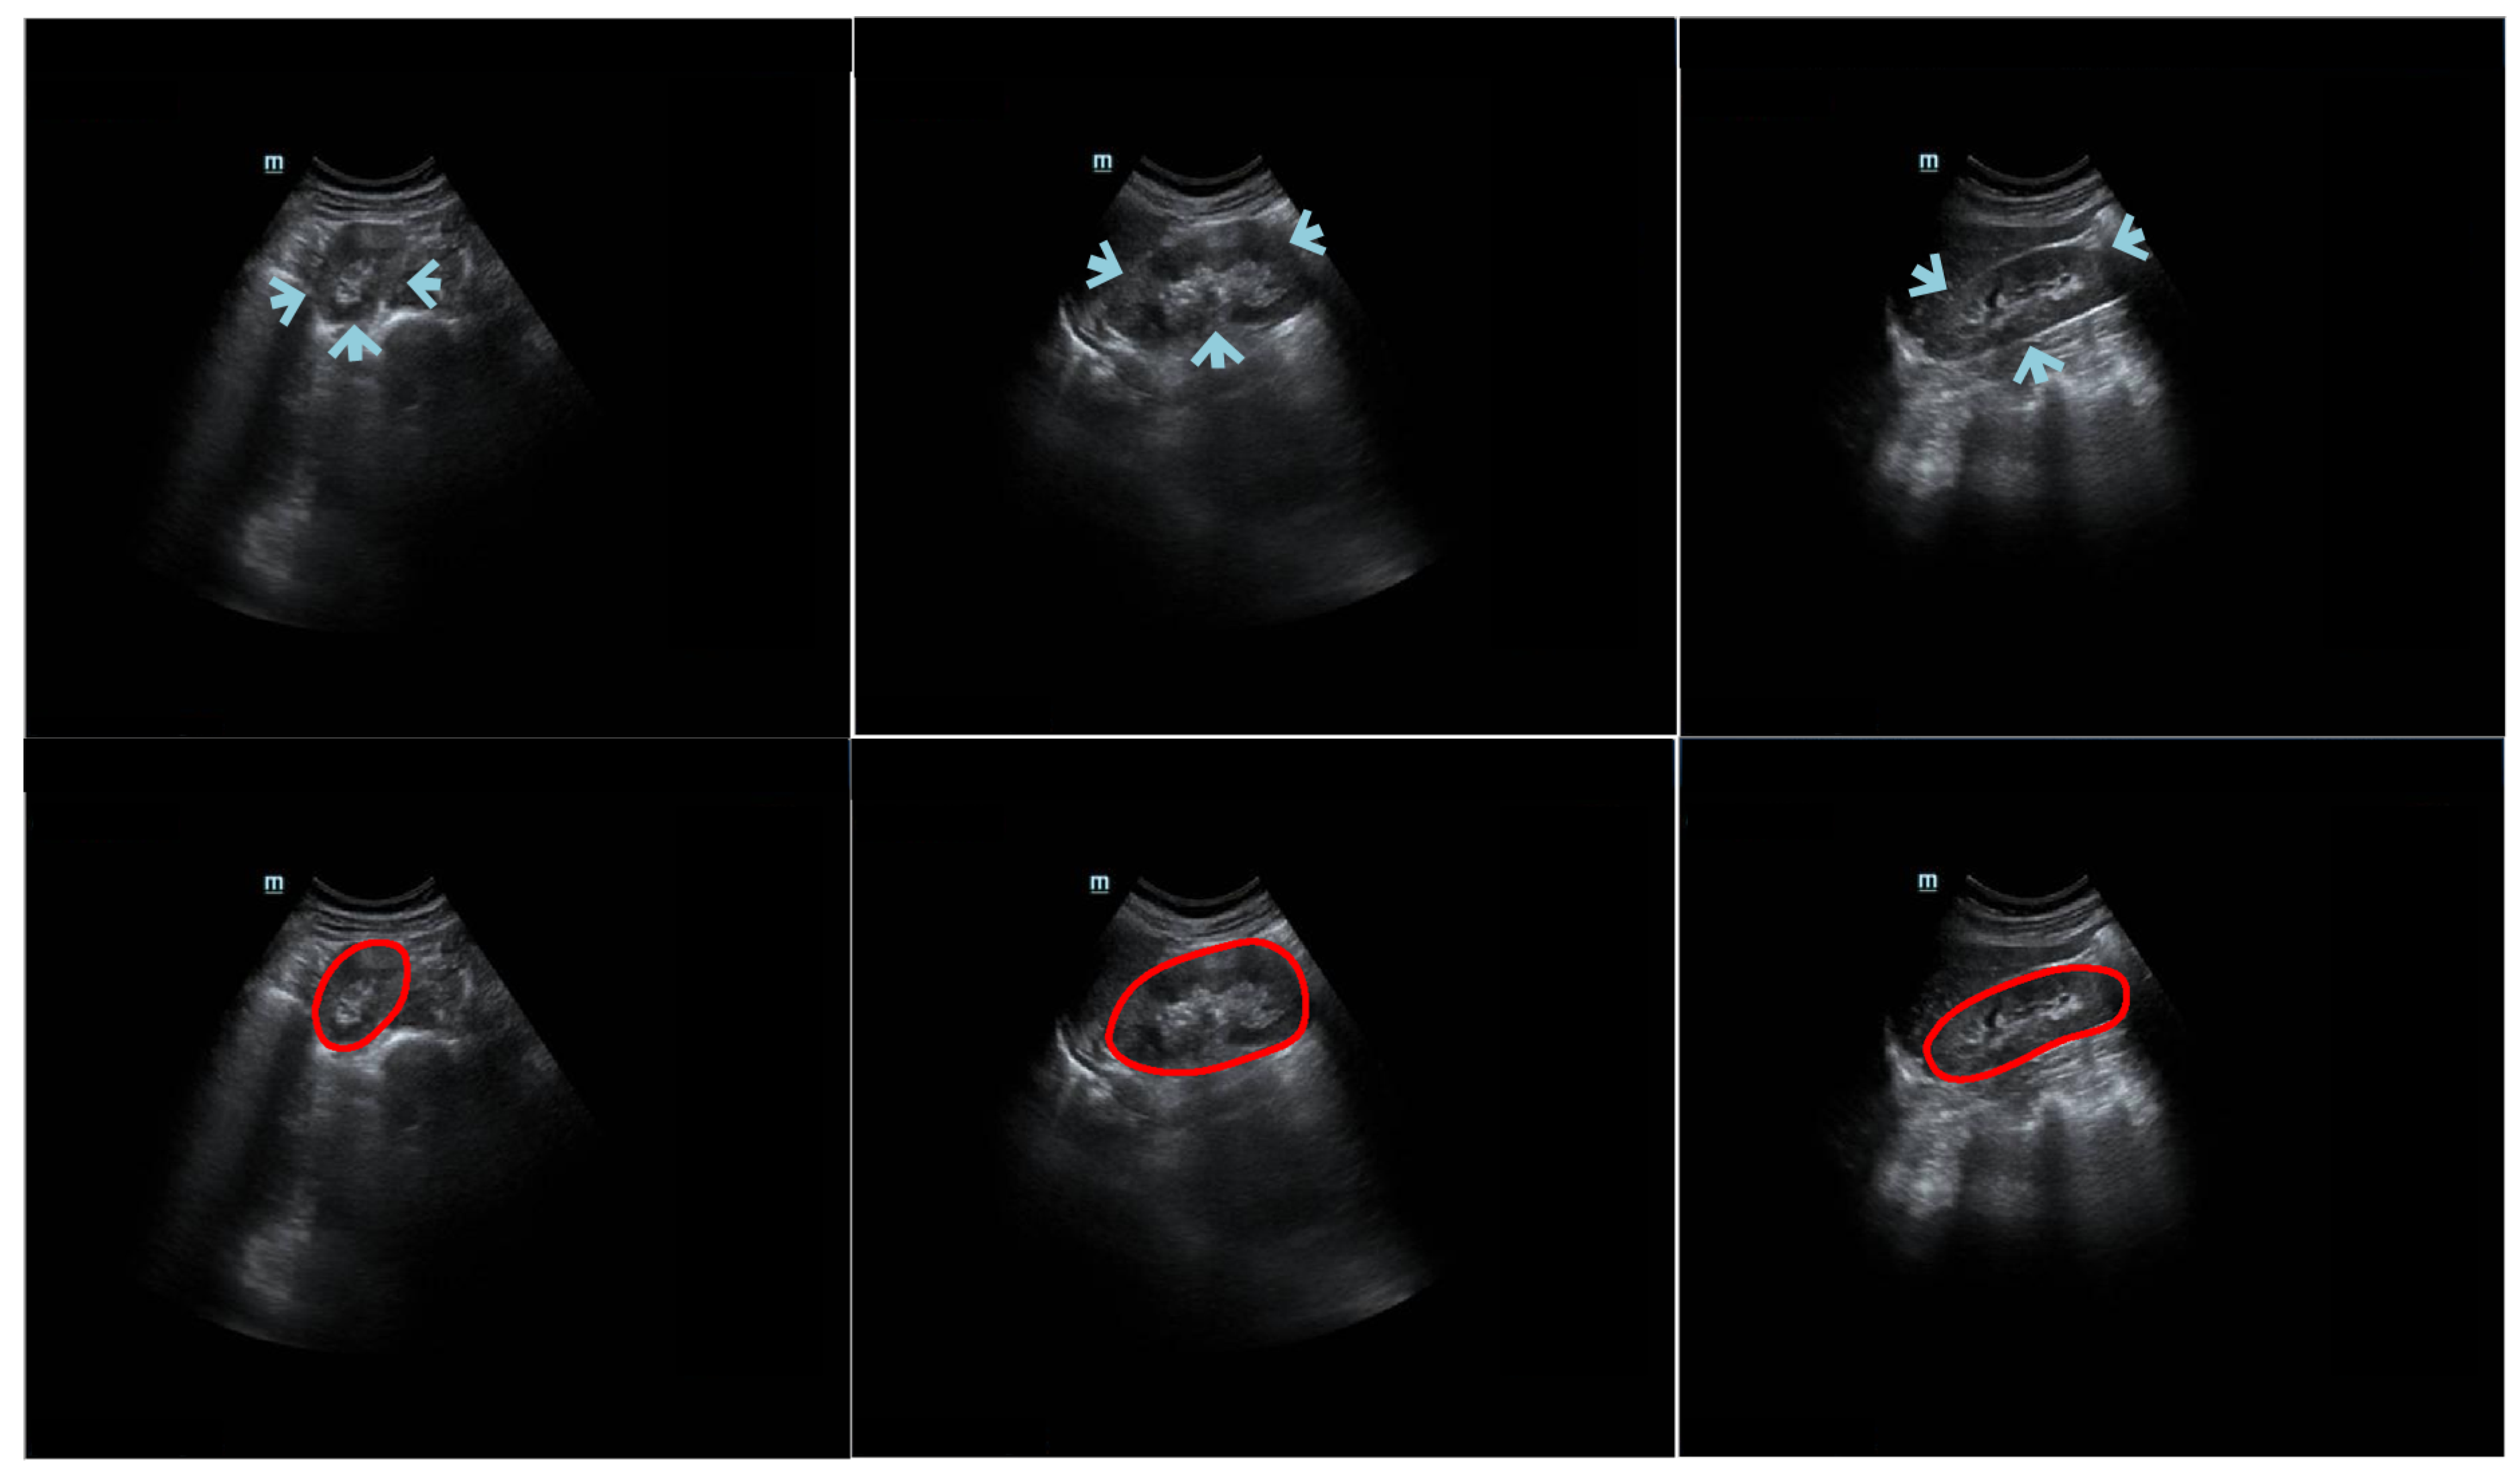

Kidney segmentation algorithms are routinely used to extract regions of interest (ROIs) from entire medical images and help radiologists make clinical decisions [1]. Given its advantages of being painless, noninvasive, and cost-efficient, ultrasound (US) imaging is a good option for evaluating kidney health [2]. However, manually labeling US kidney images is tedious and complex. To reduce the workload of radiologists and increase the efficiency of annotation, there is a demand for an automatic US kidney segmentation algorithm for clinical applications [3]. It is challenging to develop such an algorithm because (1) the kidney boundary may not always be complete and prominent due to interference from neighboring tissues (e.g., intestinal gas) [4]; (2) the kidney boundary may have low contrast; (3) the intensity of the kidney structure may follow different distributions; and (4) kidney shape varies across patients. The challenges of kidney segmentation in trans-abdominal US images are illustrated in Figure 1.

Figure 1. Example trans-abdominal US kidney images. Portions of the kidney boundary, pointed to by arrows, do not have high contrast with the surrounding tissue. The first column shows an axial image, and the second and third columns show sagittal images. The second row displays the corresponding ground truth of the original data in the first row. The red circles represent the contour manually delineated by the professional radiologists.